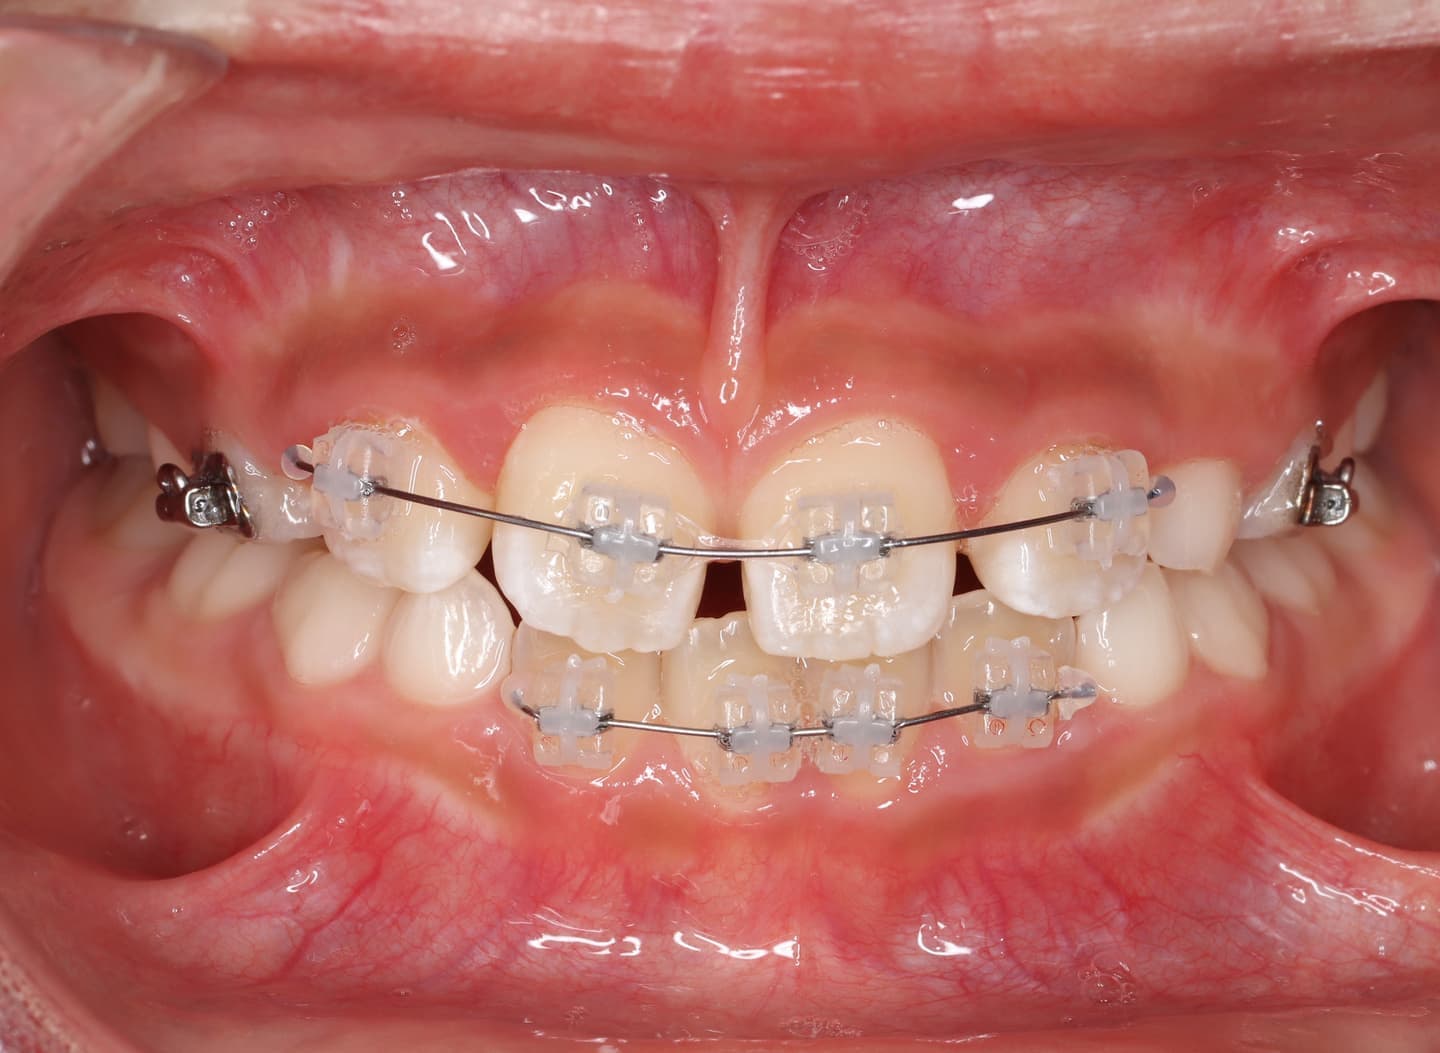

治療法:拡大プレート+フルパッシブブラケット(クリアスナップ)

治療中